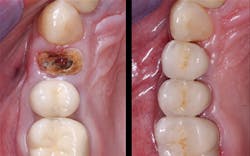

5. All tooth structure gone to the bone. Endodontic treatment. Post and core placed. Not enough tooth structure to provide a ferrule. Nonabusive occlusion (Figures 3 and 4)-Orthodontic tooth extrusion is a technique seldom used in dentistry, but it can possibly save such teeth. In spite of being taught to dental students, I find in my CE courses that orthodontic tooth extrusion is seldom accomplished. If the tooth root is long, the technique can be successful. Additional cost to the patient is necessary, accompanied by the time for orthodontic tooth movement, and a period of bone stabilization before restoring the tooth. Crown lengthening is another option if such treatment will not cause an esthetic challenge. Presence of abusive occlusion adds a strong negative to this clinical situation. Most dentists do not accomplish orthodontic extrusion or bony crown lengthening. Therefore, removal of the tooth and placement of an implant remain as the most predictable and viable solution.